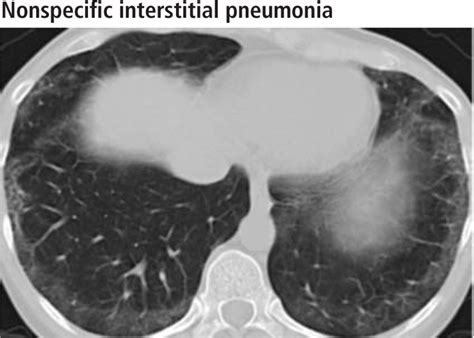

Receiving medical imaging results can often feel overwhelming, especially when terms like lung scarring on CT scan appear on your radiology report. Finding evidence of scarring—medically referred to as pulmonary fibrosis or interstitial lung abnormalities—can trigger anxiety, but it is important to remember that these findings are descriptive and require clinical context to be fully understood. A CT scan is a highly sensitive diagnostic tool that provides a detailed cross-sectional view of the lungs, allowing doctors to identify changes in the lung tissue that might not be visible on a standard chest X-ray. Understanding what this scarring means, why it happens, and what steps you should take next is the first step toward managing your respiratory health effectively.

When a radiologist identifies lung scarring on CT scan, they are typically referring to the presence of fibrotic tissue. In a healthy lung, the tissue is delicate, thin, and elastic, allowing it to expand and contract effortlessly with every breath. When injury occurs, the body attempts to repair the tissue; however, in certain conditions, this repair process goes awry, leading to the buildup of excess connective tissue.

This scarred or thickened tissue is less flexible than healthy lung tissue. Over time, as this scarring accumulates, it can make the lungs stiff, making it more difficult for oxygen to pass from the air sacs (alveoli) into the bloodstream. This physiological change is what leads to symptoms such as shortness of breath and a persistent, dry cough.

When your doctor discusses lung scarring on CT scan, they are looking at specific patterns that tell a story about the lung’s history. Radiologists often use specific terminology to describe the appearance of these changes. Here is a simplified table of common radiological findings and their general implications:

Radiological Term What It Usually Implies

Reticulation A net-like pattern indicating mild thickening of the lung structure.

Honeycombing Clusters of cystic air spaces; often suggests advanced or established scarring.

Ground-Glass Opacities Hazy areas; these may indicate active inflammation that could be reversible, rather than permanent scar tissue.

Traction Bronchiectasis The pulling open of airways due to the contraction of surrounding scar tissue.